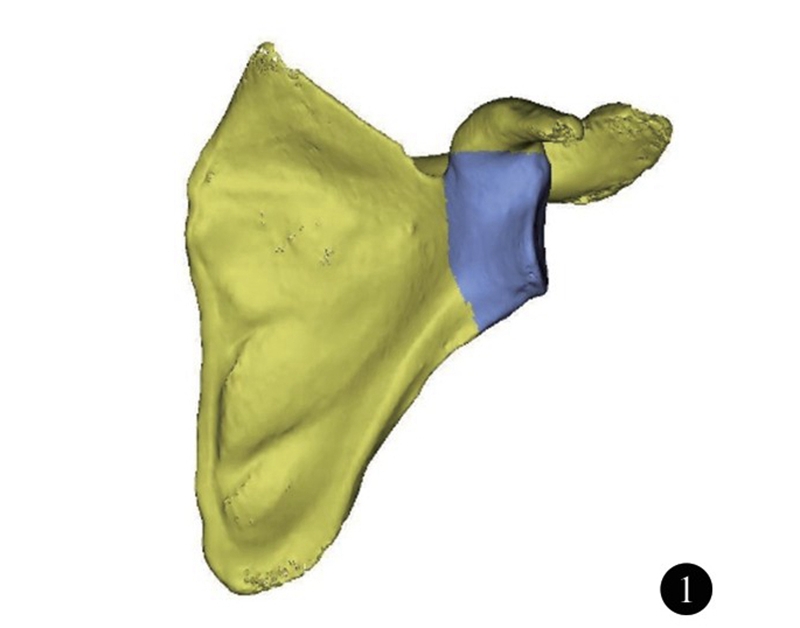

肩胛盂近似梨形,下半部分较上半部分大。在反式肩关节置换术中,肩胛盂侧假体安装在肩胛盂下部,因而肩胛盂下半部分的大小决定了假体的大小。韩国Ji等测量了本国肩胛盂下部的解剖学参数,其中肩胛盂下部半径男女分别为(17.1±2.1)mm和(15.4±1.6)mm,性别之间差异有统计学意义(图4)。

图4 肩胛盂下半部分半径(R)示意图